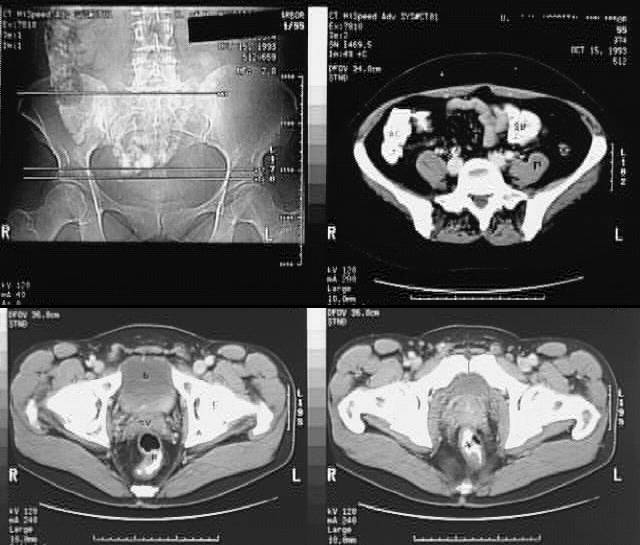

Pelvis & Perineum: Pelvis CT Cross: